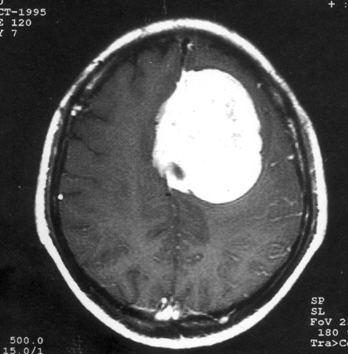

问题 病历摘要:??患者女性,37岁。大便时突起炸裂样头痛3小时,伴喷射样呕吐。既往体健。体检:T37.5℃,BP145/90mmHg,R20次/分,P85次/分。神志清楚,颅神经检查无异常,颈强直,克、布氏征(-),四肢肌力、肌张力正常,病理征(-)。 目前一般认为颅内动脉瘤形成的病因主要有哪些?提示:入院后?10小时行DSA检查,发现前交通动脉瘤